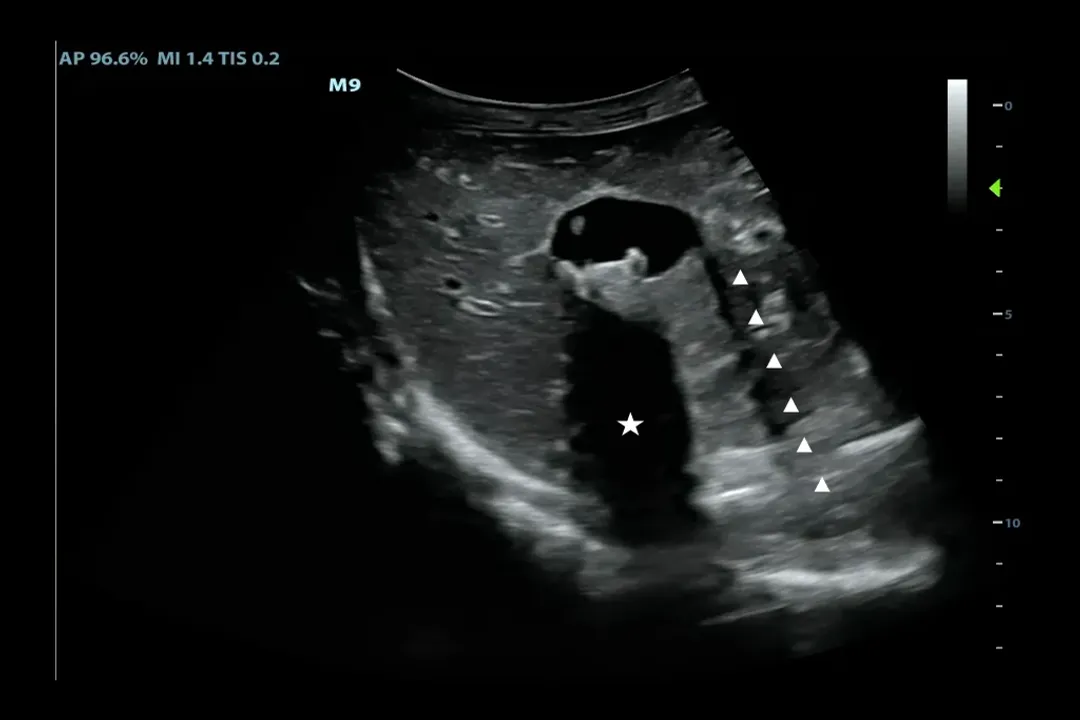

Once the sound pulse enters the body, it travels through tissues until it encounters a boundary between two different types of material—for instance, between fluid and soft tissue, or soft tissue and bone. [1][7] At these interfaces, some of the sound energy is reflected back toward the transducer as an echo, while the rest continues deeper into the body until it hits another boundary or dissipates. [7][8]

The transducer captures these returning echoes. [5] The machine then measures two critical factors for each echo received:

1. Intensity (Strength): How strong the returning echo is tells the computer about the tissue interface. Strong echoes come from boundaries where the acoustic properties change dramatically, such as the boundary between liver tissue and fluid-filled cysts or between tissue and bone. [1][7] Weaker echoes come from softer transitions.

2. Time of Flight: The time it takes for the echo to return dictates how far away the reflecting structure is from the probe. [5][8] Sound travels at a known, relatively constant speed through soft tissue (approximately 1540 meters per second). [5][8] By multiplying this speed by half the round-trip time, the system precisely calculates the depth of the structure. [5]

The sophistication of the ultrasound system lies in its computer processing unit, which takes these thousands of data points per second—time, intensity, and location—and constructs a two-dimensional visual representation in real-time. [1][8]